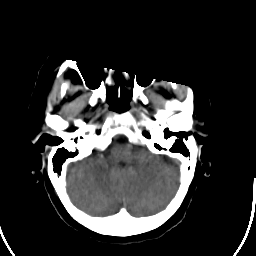

Stroke CT #1 -- Slice #4

[Home][Help][Clinical] Slice 4